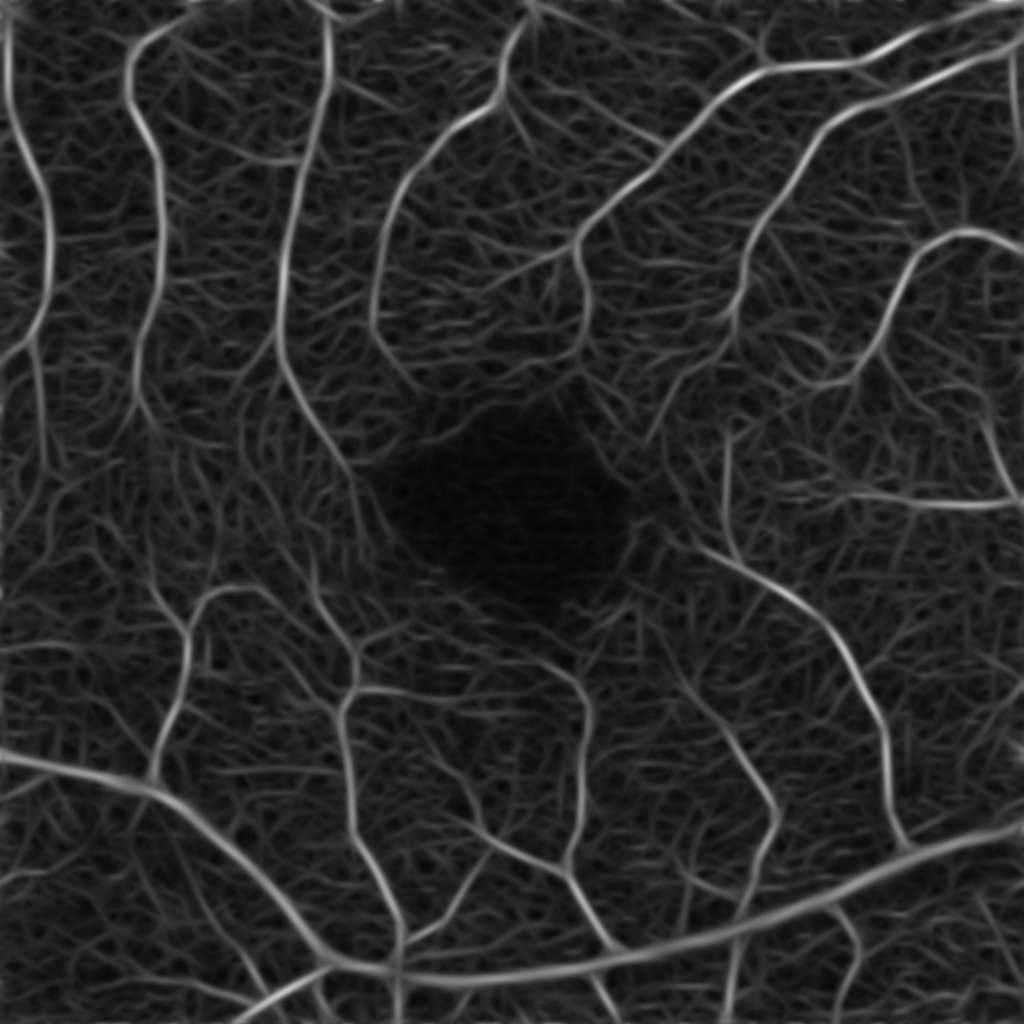

for some chosen frequency ω𝜔\omega, orientation θ𝜃\theta and σ1subscript𝜎1\sigma_{1}, σ2subscript𝜎2\sigma_{2} correspond to the spatial widths of the filter, which is then applied to an image. Here, we choose the parameters as suggested in [19] and use 333 frequency scalings {ωi}i=13superscriptsubscriptsubscript𝜔𝑖𝑖13\{\omega_{i}\}_{i=1}^{3} and 666 orientations {θj}j=16superscriptsubscriptsubscript𝜃𝑗𝑗16\{\theta_{j}\}_{j=1}^{6} to create our Gabor filter bank. The 36=1836183\cdot 6=18 computed Gabor filters are then convolved with the original image Im×n𝐼superscript𝑚𝑛I\in\mathbb{R}^{m\times n} to derive the new image representations in m×nsuperscript𝑚𝑛\mathbb{R}^{m\times n}. Next, for fixed ωisubscript𝜔𝑖\omega_{i}, we take the pixel-wise maximum in the images corresponding to the 666 orientations {θj}j=16superscriptsubscriptsubscript𝜃𝑗𝑗16\{\theta_{j}\}_{j=1}^{6}, leading to 333 images I1,I2,I3subscript𝐼1subscript𝐼2subscript𝐼3I_{1},I_{2},I_{3} with different emphasized frequency ranges, see Figure 1. These new representations are our basis for the further processing.

Figure 1: New image representations are obtained by the convolution of the original image I𝐼I with Gabor filters. The images I1,I2,I3subscript𝐼1subscript𝐼2subscript𝐼3I_{1},I_{2},I_{3} correspond to the 333 chosen frequency ranges defined by {ωi}i=13superscriptsubscriptsubscript𝜔𝑖𝑖13\{\omega_{i}\}_{i=1}^{3}.

Our image segmentation is divided into three subtasks: the identification of small and big vessel and the FAZ. The final result, see Figure 2(b), is obtained by uniting the binary images with the small and big vessels and subsequently using the FAZ segmentation as a mask that excludes that area.

For the image processing steps that focus on the identification of the small and big vessels, we will use the image representation I2subscript𝐼2I_{2} that emphasizes the medium frequencies. These frequencies correspond best to the vessels we aim to identify and therefore the new representation reveals a more clear structure of the relevant characteristics. We smooth the image I2subscript𝐼2I_{2} by convolution with a Gaussian filter